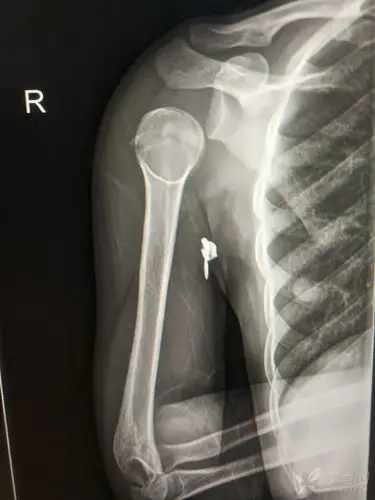

肱骨近段骨折合并肩关节半脱位 [病例帖]